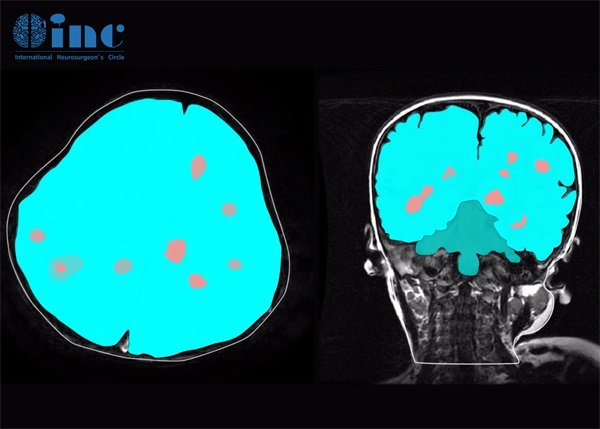

脑海绵状血管瘤怎么检测?脑海绵状血管瘤的检测方法主要有:1. 磁共振成像(MRI)、2. 计算机断层扫描(CT)、3. 血管造影(DSA)等。脑海绵状血管瘤是一种血管性病变,通常位于大脑,可能会引起多种神经系统症状。由于其相对隐匿的特性,早期诊断显得十分重要。

磁共振成像(MRI)是检测脑海绵状血管瘤的首选方法。MRI能够提供高分辨率的脑部影像,帮助医生清晰地观察到各类脑部病变。

在检测中,MRI可以明确显示海绵状血管瘤的形状、大小,以及位置。通过采用T1加权和T2加权成像,可以更好地识别病变的特征。此外,MRI对周围脑组织的影响和病灶的水肿情况也有良好的显示效果。

脑海绵状血管瘤微出血

脑内海绵状血管瘤的微出血是指小血管破裂后,血液渗入周围脑组织,通常不会出现明显的临床症状。

对于已知存在脑海绵状血管瘤的患者,医生会定期进行MRI监测,以观察微出血的情况。